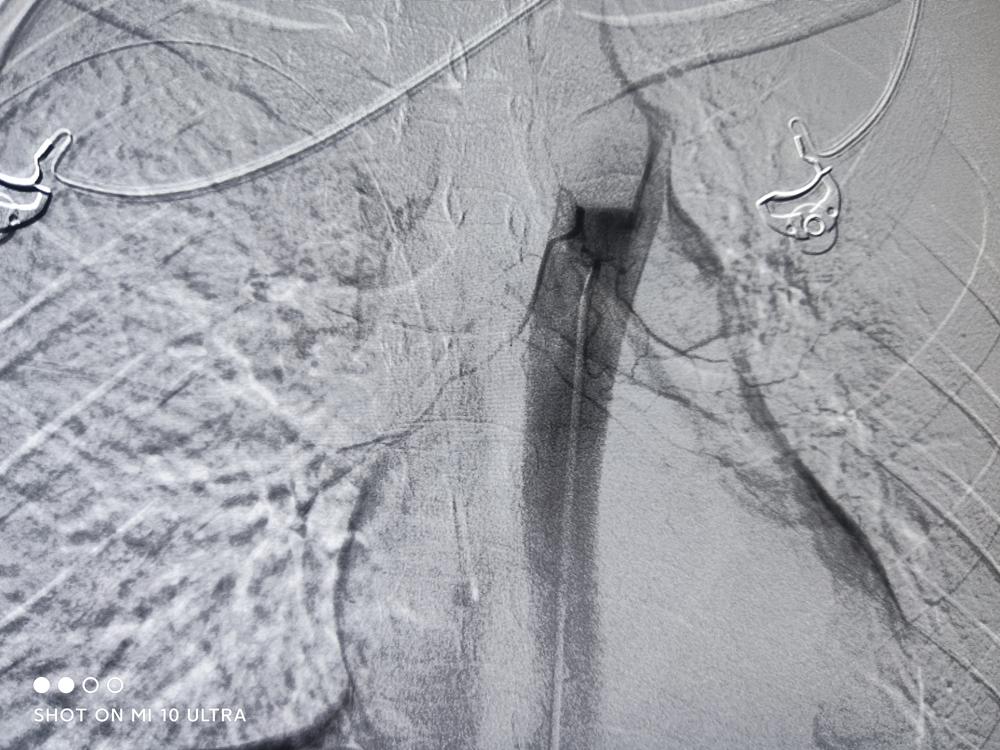

患者的检查报告

经过我院一个疗程的血管靶向治疗,患者的肿瘤得到了控制,有了一定的好转。现在患者为行第2疗程治疗,再次来到医院接受治疗。